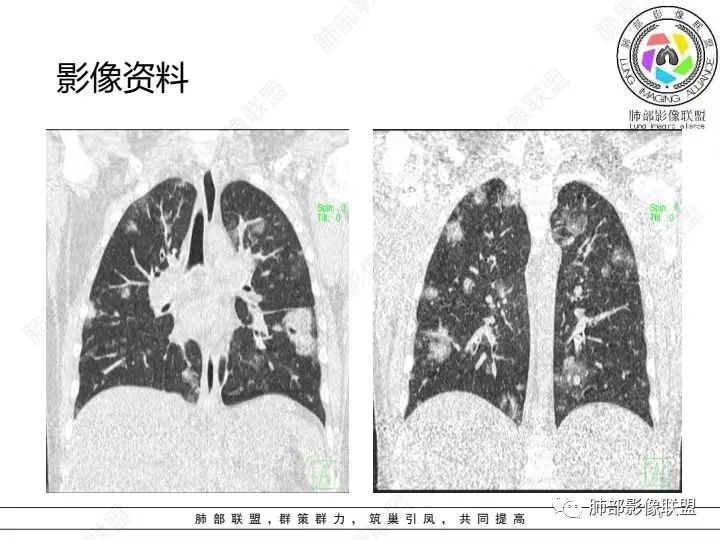

少年患者,游泳后发热畏寒,呼吸困难,两肺弥漫分布结节及磨玻璃影,考虑寄生虫感染,钩体病?

外伤后与河水接触史,病灶分布随机,点晕征,淋巴低,CRP、降钙素高。休克血压。考虑感染性病变:钩端螺旋体病

青少年,高处跳落游泳史,左侧盆部疼痛(怀疑皮肤损伤),畏寒发热,CRP和Pct显著升高,感染性休克表现(提示革兰阴性杆菌),双肺叶外周分布为主棉絮状结节及斑片影,GGO密度,边缘清,间质及实质改变,病灶内细网格影,见供血血管证,分布特点双肺叶Spe表现,考虑大肠杆菌导致血行感染,血培养检查!

男14岁,2天前下河游泳史,发热;两肺近外带可见磨玻璃密度影,边缘疑似晕征,结合实验室检查,符合感染,倾向真菌感染,支持肺钩端螺旋体病。

青少年,2天前下河游泳后畏寒发热,两肺外周胸膜下分布多发大小不等结节、斑片及磨玻璃,边缘模糊,考虑血流性感染,钩体?金葡?

青少年男性,2天游泳后发热,双肺多发斑片状,结节状阴影,多分布肺外带,血道来源,部分病灶边缘可见磨玻璃影,患者有明显脂肪肝病史,考虑.感染性病变,金黄色葡萄球菌?钩体?肺克?

青少年,河沟游泳后急性发病,左侧髋部疼痛,双肺弥漫地方结节、斑片模糊影,CRP、PCT明显增高,考虑钩体病,鉴别血播金葡

PCt>200,脓毒血症了,有无皮肤损伤?诱因游泳,高处跳水,与水有关,影像为多发毛玻璃结节,有细网格样改变,内可见支气管影,所以是间质改变➕肺泡渗出;结节分布是随机分布,血源性。与临床相对应。感染性病变,pct不支持病毒排除。细菌,金葡?军团?需复查看看病情转变。有无三红三痛,如有,钩也可能。寄生虫待排。

年轻患者,急性起病,高处跌下,皮肤损伤,两肺胸膜下多发实变,边缘见磨玻璃影,部分实变呈楔形,实变内见粗网格影,部分实变见反晕征,综和病史考虑感染性病变,影像上符合脓毒性肺栓塞,支持血源性金葡菌感染,鉴一下COP

青年人,有游泳史,畏寒发热,双肺内及胸膜下多发实变,边缘见磨玻璃密度影,部分呈反晕征,内可见多发网格样改变,考虑感染性病变,金葡菌感染

双肺叶结节及斑片状磨玻璃样密度,边缘清,外周分布为主,部分见供血血管,分布特点符合Spe表现,青少年,高处跳落游泳史,左侧盆部疼痛,畏寒发热,CRP和Pct显著升高,考虑血行感染,金葡?至于大家考虑的钩端螺旋体病和嗜水单胞菌不是太了解

青少年发病急,高热,双肺多发斑片状磨玻璃影,边界模糊,以胸膜下为主,考虑感染性病变,金葡菌可能

青年,游泳,盆骨处疼痛”原因?”,畏寒,发热,Pct明显升高。双肺多发斑片,结节影。胸膜下也有。考虑血播。金葡可能大

分布,胸膜下和支气管束分布 密度以磨玻璃为主 ➕小叶内间隔增厚细网格征 出血?病毒性感染?

男,14岁,高处跳下,游泳后畏寒。胸部CT:两肺多发斑片影、结节影;沿支气管血管束分布,胸膜下也有;密度以GGO为主,部分为mGGO;边缘部分清楚,大部分模糊;内可见网格影、支气管充气征。考虑:SPE?肺水肿?鉴别淋巴瘤。

2.影像上肺多发混合密度片影,随机分布,胸膜下分布优势,病灶边界大多隐约可辨,偏柔和,动脉血管影穿行,未见钙化、液化空洞、或明确气囊影,未见树芽征。

3.双侧胸腔未见积液。双肺门及纵隔未见增大淋巴结。

4.肝左右叶密度减低,未见结节影、块影或液化区。

3.影像方面:双肺多发病灶,随机分布,且有相当部分沿胸膜下,是可以符合血流感染的。

1.外围分布,胸膜下为主,两肺弥漫结节或胸膜下楔形影,边界清,周围伴有GGO